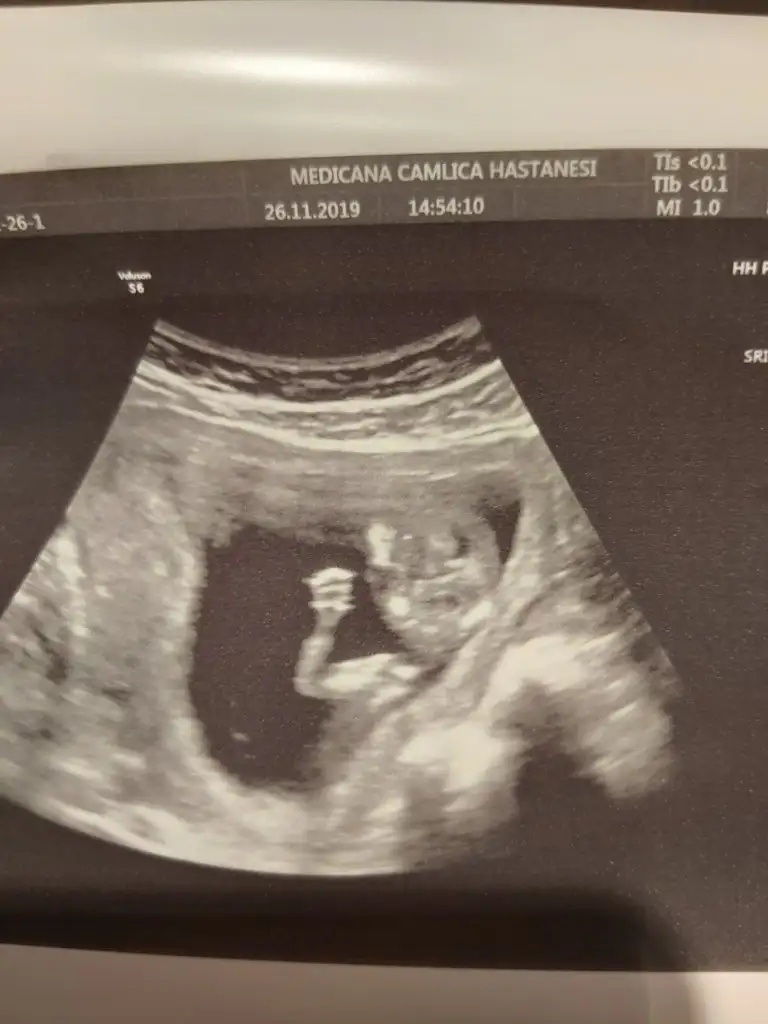

Maşallah :) bana 12+4'te cinsiyet tahmini yaptı. Bir dahaki kontolüne çikolata yiyerek git ikili teste :) kıpır kıpır oluyor gösteriyor o zaman :)Kızlar herşey yolunda çok şükür önde çıktık biraz oturuyor bizimki bildigin göstermedi iyi dedi bebiş iyi kalp atışı iyi 12+4 çıktık..Bu arada ikili test ve kan istedi ama 600 tl fiyat verdiler çok pahalı geldi oyuzden birkaç tane daha hastaneye sorcam ama yaptırcam ben sanırım.

Doktoru soranlar olmuştu medicana dr.hüseyin arık herşeyi sordum gönül rahatlığıyla güler yüzle gayet iyi bir dr devam edicem doktorumu buldum çok şükür tavsiye ederim dr çok önemli sizi dinliyor motive ediyor.